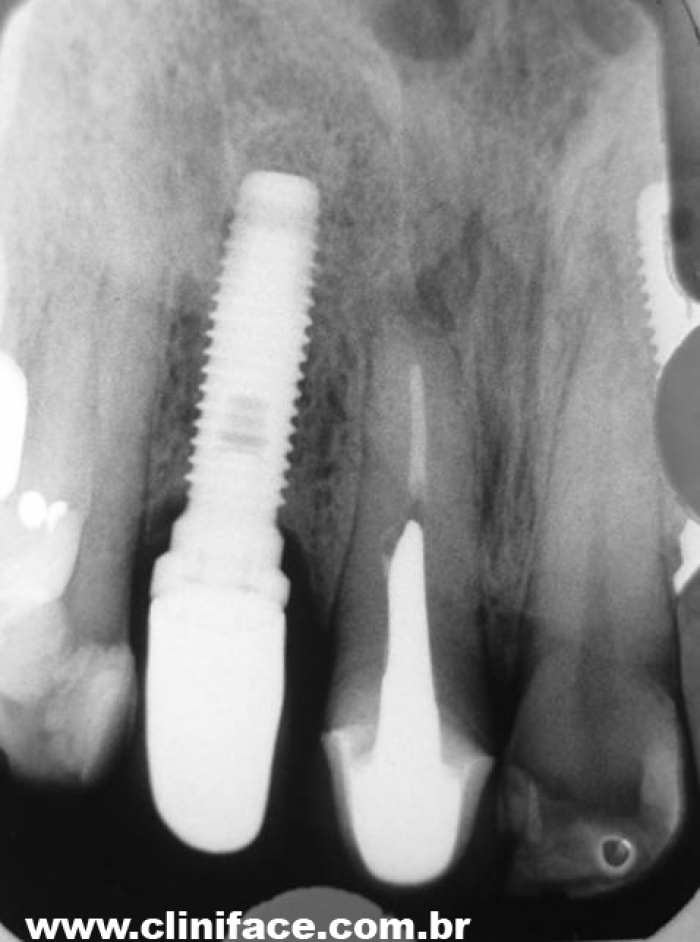

Rx atual (2009) de Implantes Nobel® e Próteses Instaladas nos elementos 12 e22, em 1998